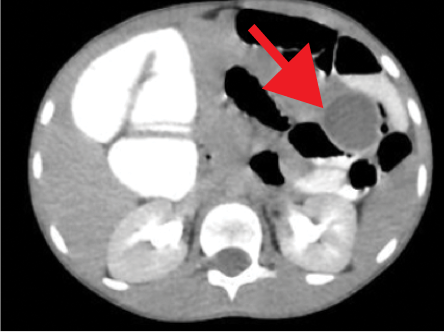

The contrast-enhanced computed tomography (CECT) abdomen findings were as follows: The D3 segment of the duodenum was seen to cross to the left side with the duodeno-jejunal junction in its expected location. The superior mesenteric arter-superior mesenteric vein (SMA-SMV) relationship was maintained with the SMV lying on the right side of SMA. The small bowel loops were predominantly on the left side of the abdomen, and the entire colonic loops were positioned on the right side of the abdomen [Figure 1]. The ileocecal junction (ICJ), cecum, and appendix were noted in the right lumbar region [Figure 2]. The inferior mesenteric artery was seen coursing to the right side of the midline, rather than its normal left-sided course [Figure 3]. A tubular cystic lesion was observed in relation to the small bowel loops on the left side of the abdomen [Figure 4]. Intrabdominal solid organs were essentially normal, with a normal situs.

Figure 4: Axial sections of contrast-enhanced computed tomography abdomen showing a well-defined fluid filled cyst (red arrow) on the left side of the abdomen in relation to the small bowel loops.

Figure 4: Axial sections of contrast-enhanced computed tomography abdomen showing a well-defined fluid filled cyst (red arrow) on the left side of the abdomen in relation to the small bowel loops.